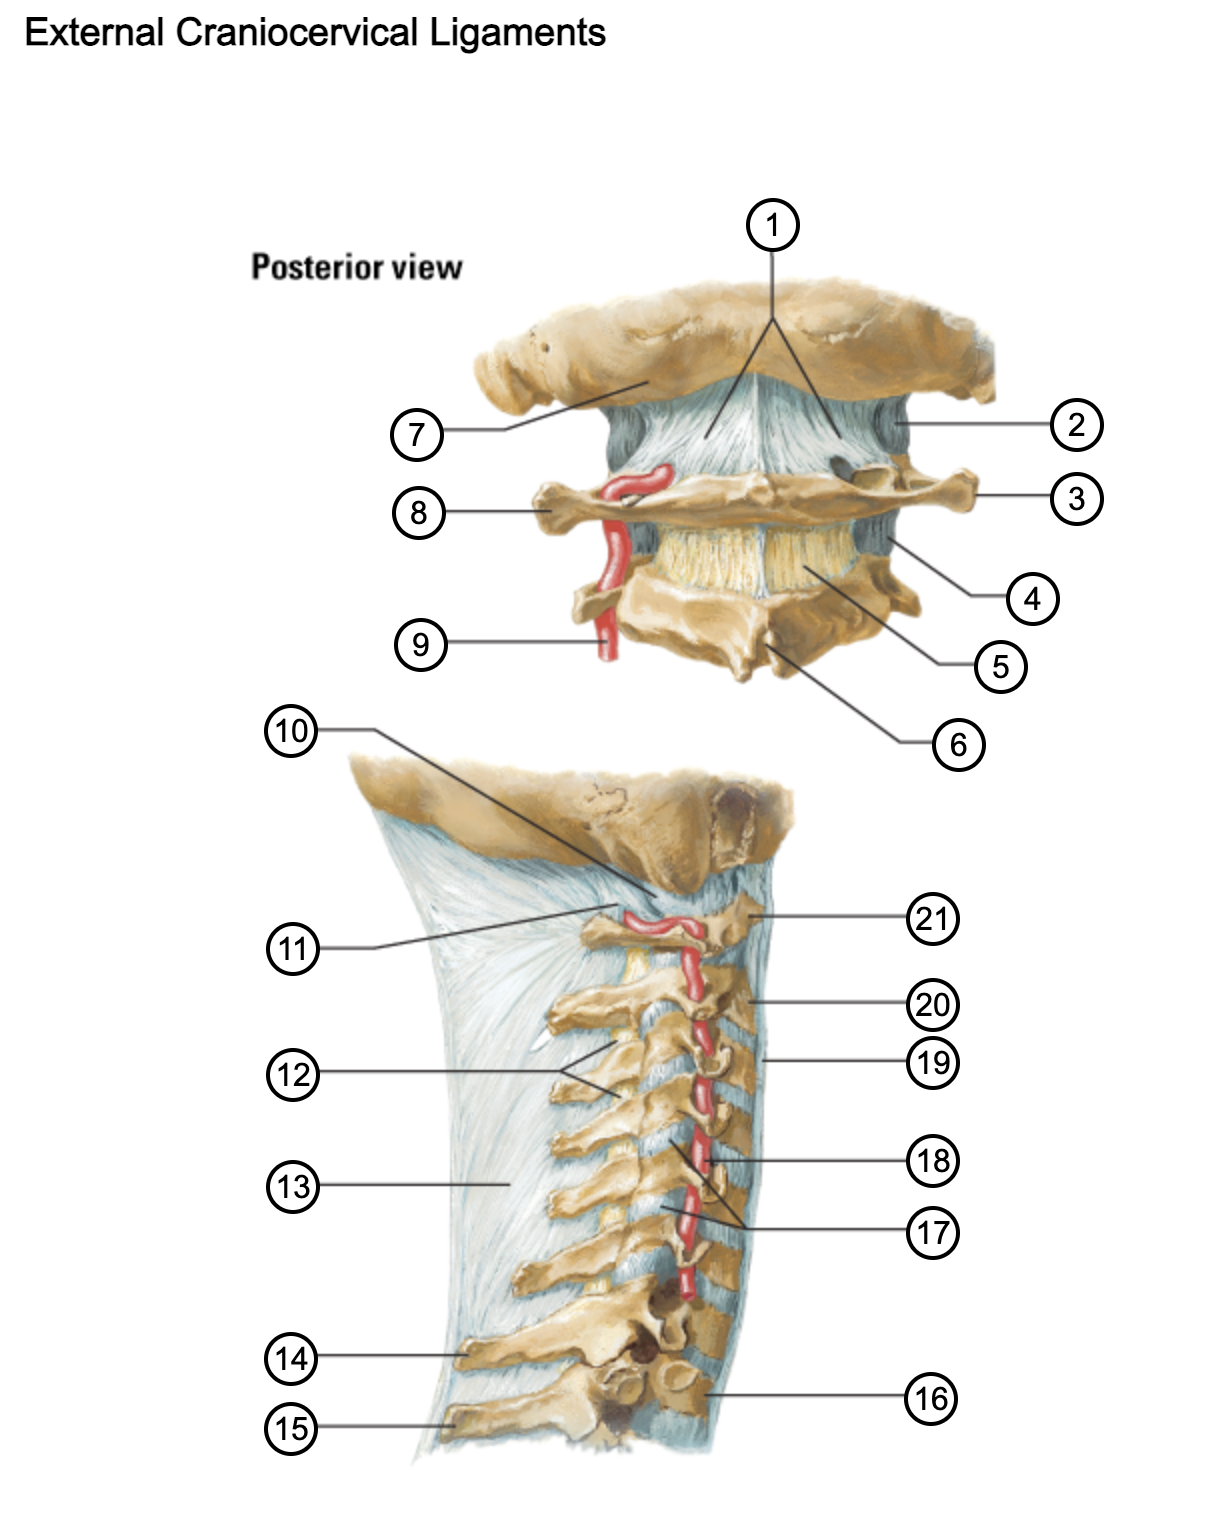

1

posterior antlantooccipital membrane

2

capsule of atlantooccipital joint

3

transverse process of atlas (C1)

4

capsule of lateral atlantoaxial joint

5

ligamenta flava

6

spinous process

7

occipital bone

8

transverse process of atlas (C1)

9

vertebral artery

10

capsule of atlantooccipital membrane

11

posterior atlantooccipital membrane

12

ligamenta flava

13

nuchal ligament

14

spinous process of C7 vertebra

15

spinous process of T1 vertebra

16

T1 vertebra

17

zygapophysical joints (C4-5 and C5-6)

18

vertebral artery

19

anterior longitudinal ligament

20

body of axis

21

Atlas (C1)